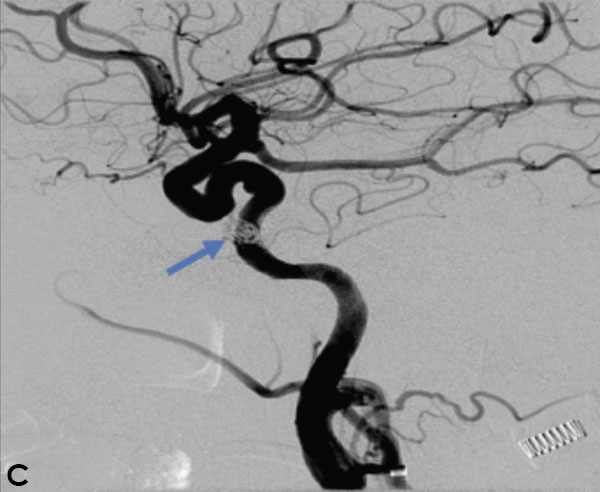

Collateral venous drainage into the orbit and skull base was observed (Figure A). After successful cannulation of the direct aperture between the right carotid artery and the cavernous sinus, balloon-assisted coil embolization of the posterolateral compartment was performed until the fistula was closed (Figure B and C). He experienced immediate cessation of his pulsatile tinnitus with an early improvement of the right VI nerve palsy and near-complete recovery of his vision within 6 weeks

Figure: (A) Right ICA Cavernous Fistula with Venous Shunting (B) Balloon Assisted Coil Embolization (C) Fistula Cured Post Embolization